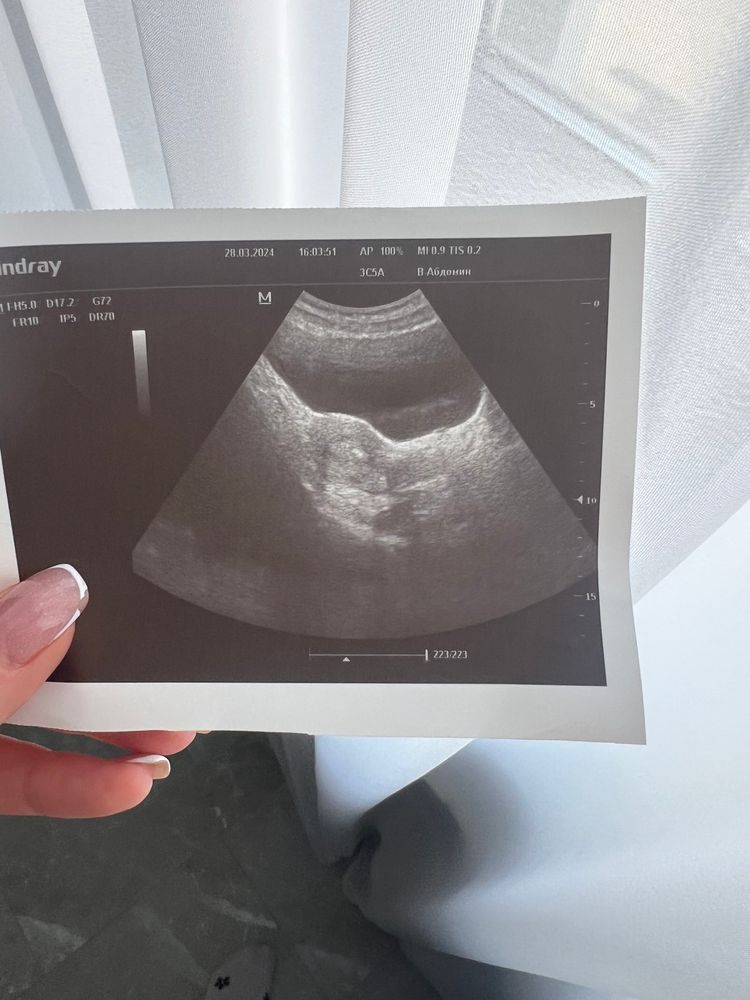

28 марта был Криоперенос

на 23 дц Криоперенос 🙌🏻